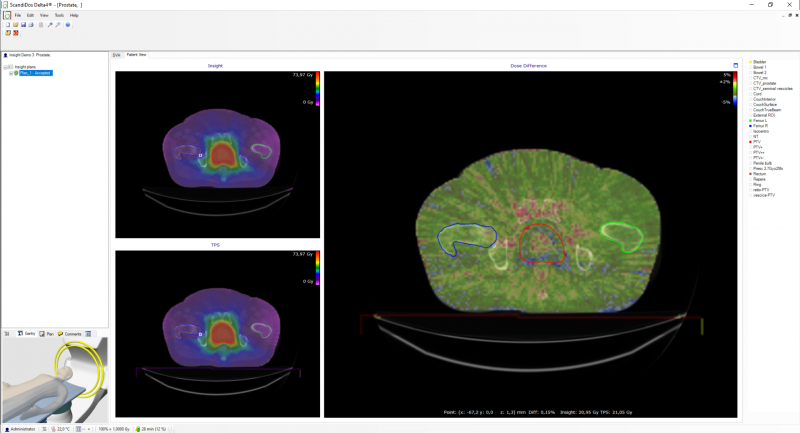

- View the Monte Carlo dose and TPS/Insight dose differences overlayed on the patient CT.

- Localize your dose differences.

- Extract point doses and dose differences